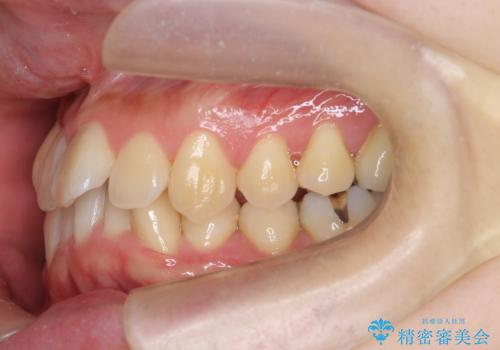

ねじれ・がたつきのある前歯を改善

見た目の改善だけでなく、噛みやすくなったことにも満足いただくことができました。

4本の小臼歯抜歯を避け、下顎前歯の1本抜歯の極力少ない抜歯本数で審美的な歯並びを得る治療計画としました。